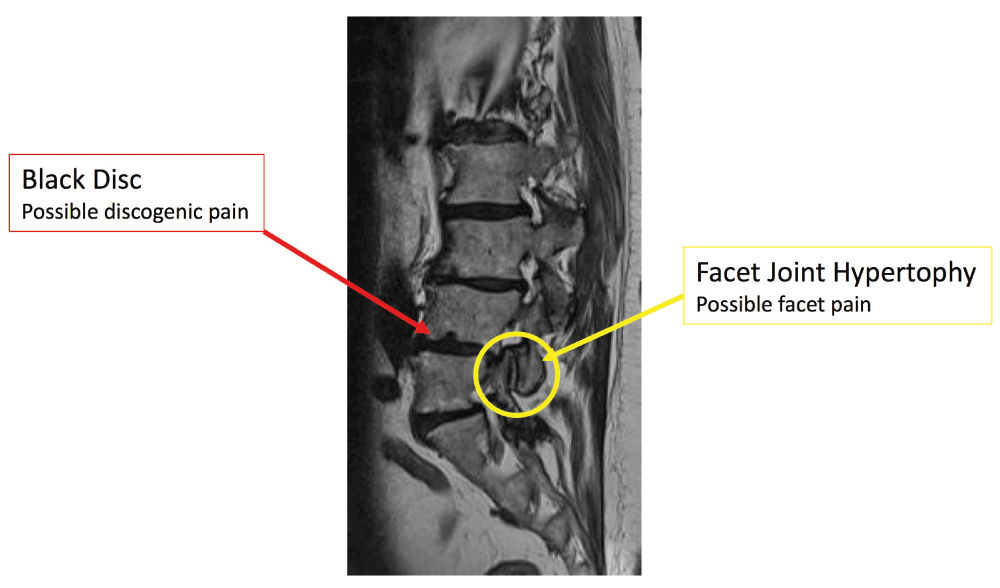

There are no pathognomonic radiological findings for the diagnosis of lumbar facet syndrome. With MRI, we can find non-specific signs of arthrosis, osteophytes, and hypertrophy of flaval ligaments. However, if we want to better study arthrosis problems, CT is the preferred imaging method, even if radiation exposure should be kept in mind56. One of the most important exams is provided by X-rays, especially dynamic projections, that can show column instability (listhesis that could be increased with flexion and extension of the low back column) with a clear overload of these joints58. In conclusion, despite the contribution from neuroimaging, history and clinical examination remain fundamental steps in the diagnosis of facet joint syndromes.

Disc degeneration (DD) has been estimated as the source of CLBP in 39% of cases82. Its symptoms are aspecific, axial, and without radicular radiation and they occur in the absence of spinal deformity or instability. DD is often a diagnosis of exclusion among other types of CLBP. Pathologically, it is characterized by the degradation, within the disc, of the NP matrix with accompanying radial and/or concentric fissures in the AF83.

Imaging MRI can detect changes in the endplates and in the vertebral bone marrow, such as edema in the vertebral bodies (Modic type 1). Clinical trials have demonstrated that some patients suffering from LBP have improvement following amoxicillin-clavulanate84,85. Moreover, diabetes increases the risk of developing painful DD because advanced glycation end products (AGEs) induce catabolism and promote inflammation86.

MRI cannot definitively demonstrate whether a disc is painful87. Provocation discography aims at reproducing patients’ pain through contrast injection during live fluoroscopy plus CT imaging for clarifying associated morphological abnormalities of the disc88. The clinical utility of discography and its diagnostic accuracy is, however, a matter of controversy because of poor specificity. Beyond the reported complications as discitis, neurologic injury, visceral injury, and dye reactions89, it’s been demonstrated that the needle puncture of the lumbar disc may lead to accelerated MRI-documented DD. The mechanism is likely multifactorial: structural damage caused by the needle, pressurization, and toxicity of the contrast media90.